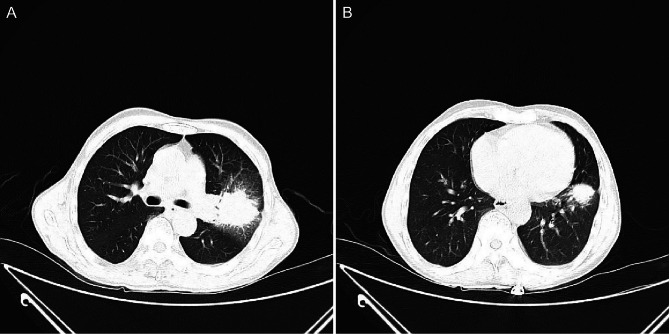

Case presentation: A 66-year-old man presented with cough, sputum, chest tightness and weight loss persisting for 1 month. Chest X-ray revealed a space-occupying lesion in the left lung. Further CT imaging demonstrated irregular soft tissue masses in both the upper and lower lobes of the left lung. Although the imaging findings suggested lung cancer, the final pathological diagnosis confirmed AFOP. The patient was treated with methylprednisolone, resulting in substantial improvement of the upper lobe lesion, whereas the lower lobe lesion showed minimal response. Following the addition of mycophenolate mofetil, the lower lobe lesion decreased substantially. Multiple lung biopsies confirmed the diagnosis of AFOP, with no evidence of a malignant tumour.

Conclusions: Acute fibrinous and organising pneumonia presents with non-specific imaging findings, and when manifesting as a mass-like lesion, it may be misdiagnosed as lung cancer. Pathological examination remains essential for diagnosis. Close monitoring of the clinical response is crucial during treatment, and the treatment plan should be tailored to individual patient needs.